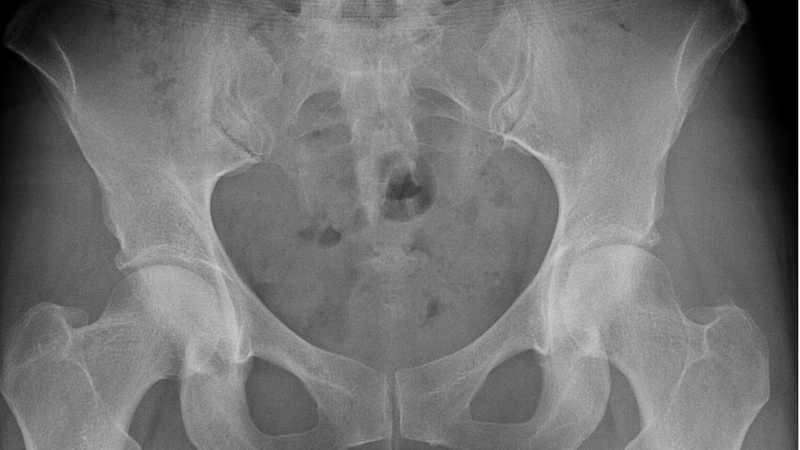

Các bác sĩ sẽ tiến hành kiểm tra sức khỏe để tìm hiểu nguyên nhân, nếu cần thiết bệnh nhân sẽ được chỉ định các xét nghiệm bổ sung. Thông thường bạn sẽ được thực hiện các xét nghiệm hình ảnh, ví dụ như chụp X-quang, quét xương hay chụp cộng hưởng từ (MRI).

Viêm bao hoạt dịch khớp háng là bệnh gì? Cách điều trị bệnh hiệu quả 4

Chụp X-quang để xác định bệnh và phương án điều trị phù hợp